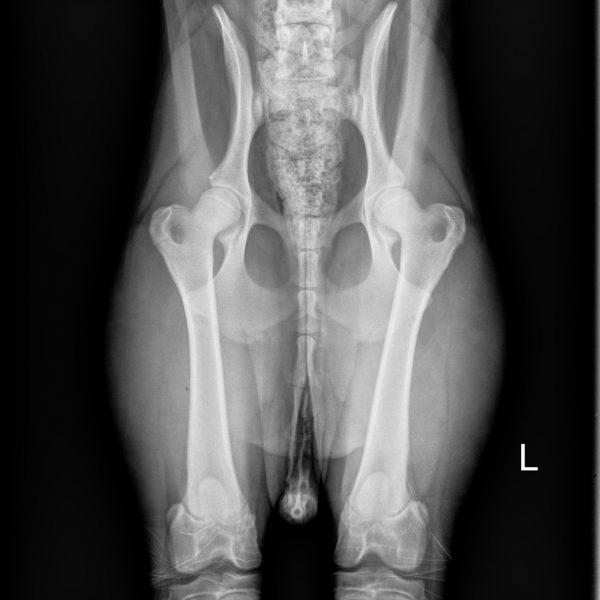

- MDBA Australian Cobberdog breeding female.

- DOB: December 18 2018.

- Height: 20 inches.

- Weight: 37.4 LBS.

Arrowhead Adsila